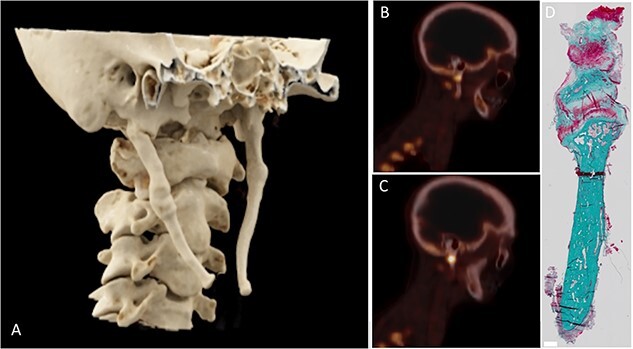

Eagle syndrome is a bone disease where elongation of the styloid process leads to throat and neck pain, and in severe cases neurovascular symptoms such as syncope and neuralgia. The pathophysiology of Eagle syndrome is poorly understood with various theories having been proposed how this elongation is caused. To better understand the pathophysiology, we performed a work-up in 6 patients presenting with Eagle syndrome. Patients mainly presented with pain on turning the neck (100%), foreign body sensation (67%), tension in the neck (67%), and dysphagia (50%). The typical length of the styloid process ranges from 25 to 30 mm; however, [18F]NaF (sodium fluoride) PET/CT showed elongated styloid processes with an average length of 52.1 ± 15.6 mm (mean ± SD) with increased turnover at the base of one of the styloid processes. The removed styloid processes were further examined by histology, micro-CT, quantitative backscatter electron imaging (qBEI), Fourier transform infrared spectroscopy (FTIR), and circularly polarized light imaging. Histology revealed one case of a fractured styloid process healing through callus formation and one case of pseudarthrosis. Bone mineral density and mineralization was similar in the styloid processes when compared to cortical bone samples derived from the mandibular bone of different patients. Circular polarized light microscopy showed a collagen orientation in the styloid process comparable to the cortical bone samples with a distinct separation of collagen structure between the mineralized structure and the surrounding soft tissue with FTIR analysis demonstrating a typical composition of bone. This altogether suggests that the elongated styloid processes in Eagle syndrome are mature bone, capable of endochondral repair, possibly growing from the base of the process through endochondral ossification, rather than being a form of secondary calcification of the stylohyoid ligament as previously postulated.